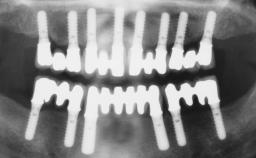

Immediate Loading of Six Implants in the Mandible and Six Implants in the Maxilla and Final Restoration with Full-Arch CAD/CAM Metal Framework FDPs Involving Digital Planning and Guided Surgery

# of Implants 12

Guided Surgery Yes